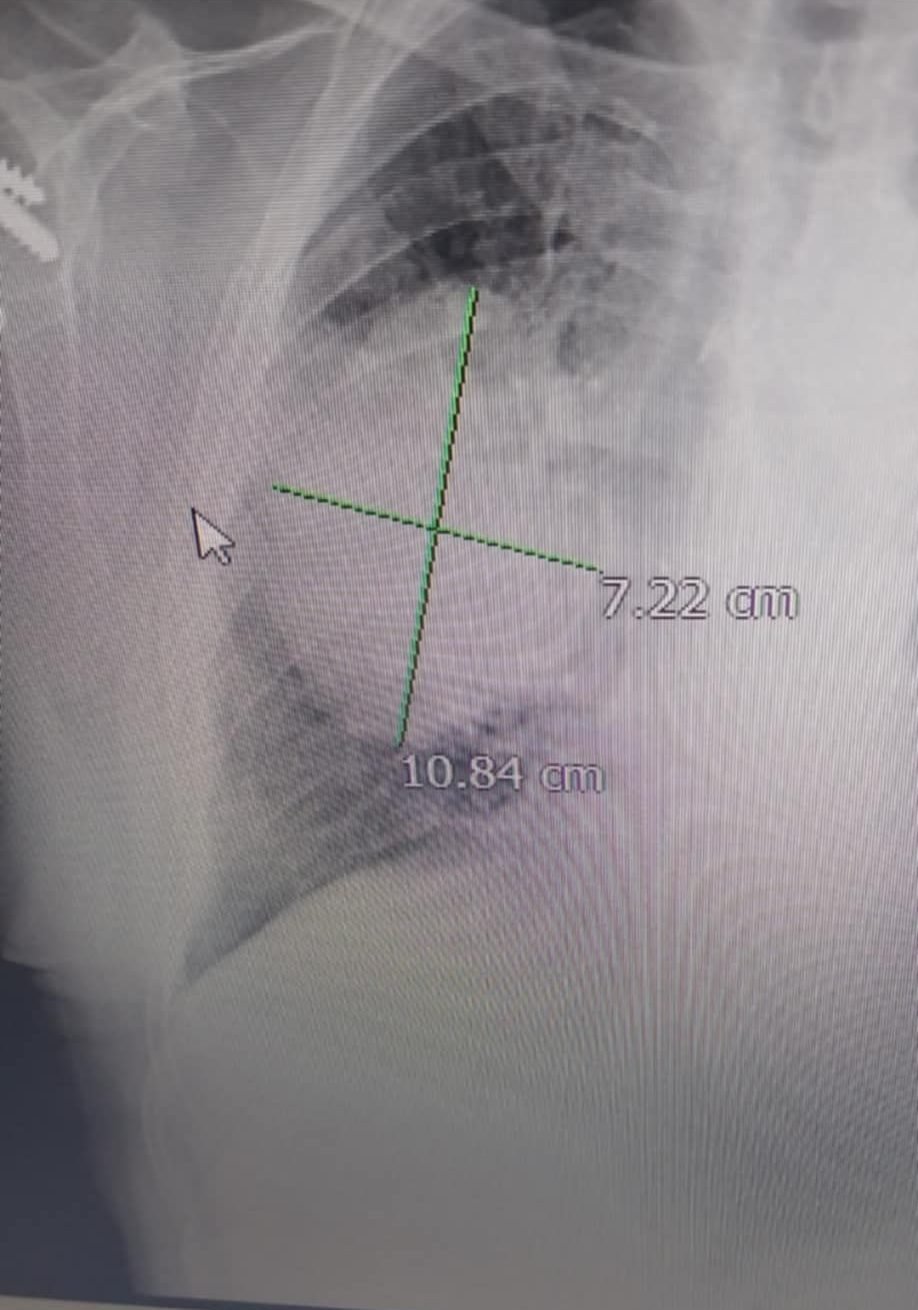

เรื่องเล่าสามีเป็นมะเร็งปอดระยะ 4 ปฏิเสธการรักษาผลมาจากการสูบบุหรี่ไฟฟ้าคาดว่าป่วยมาตั้งแต่ ม.ค. แต่ตรวจเอ็กซเรย์ (X-Ray) และซีที-สแกน (CT-Scan) จริงจังตอนเดือน พ.ค.เพราะไอเป็นเลือด ตอนนั้นพบก้อนขนาด 7 เซนติเมตร

“สามีเป็นมะเร็งปอดระยะ 4 ปฏิเสธการรักษาเป็นผลมาจากการสูบบุหรี่ไฟฟ้าคาดว่าป่วยมาตั้งแต่ ม.ค. แต่ตรวจเอ็กซเรย์ (X-Ray) และซีที-สแกน (CT-Scan) จริงจังตอนเดือน พ.ค.เพราะไอเป็นเลือด ตอนนั้นพบก้อนขนาด 7 เซนติเมตร เจ้าตัวเลยอยากทำ การเอกซเรย์ปอด (Chest X-ray) คือ การตรวจเช็คอวัยวะภายในของบริเวณส่วนทรวงอกที่ประกอบไปด้วยโครงกระดูก ปอด และหัวใจเป็นหลัก”

“เช็คทุกเดือนเผื่อกินยาสมุนไพรแล้วจะดีขึ้น แต่เปล่าเลย ! ขนาดก้อนเนื้อขยายเพิ่มเดือนละ 1.5 ซม. ตอนนี้เสียชีวิตแล้ว”